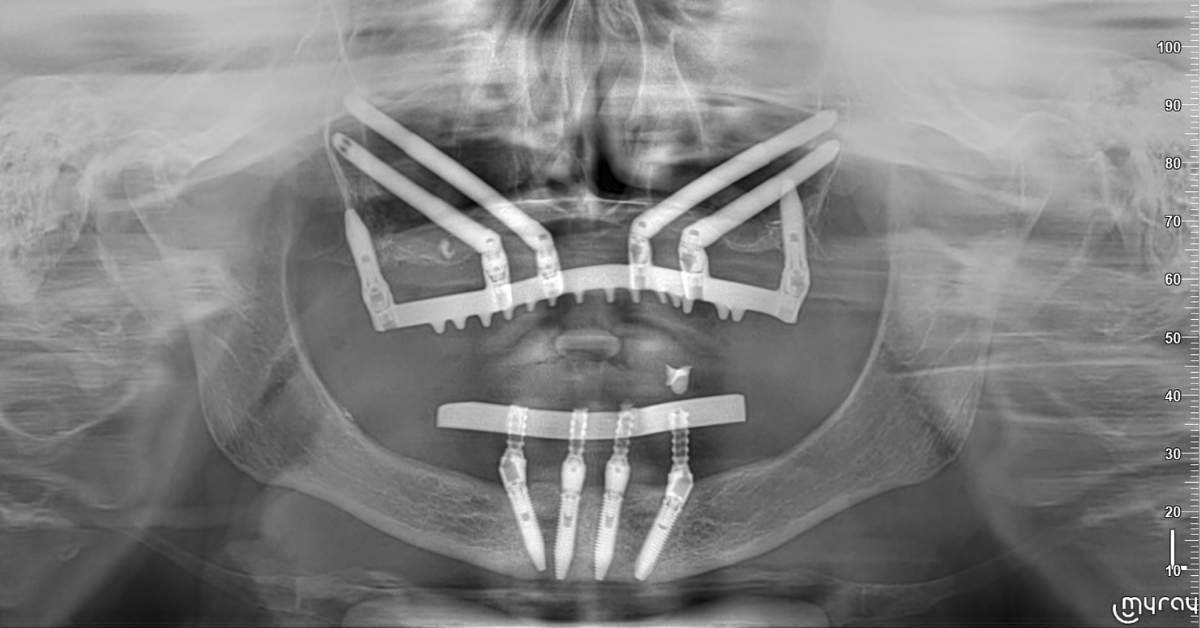

FASE 2 - Studio del repertorio radiologico (Tac – Panoramica – Radiografia) e della stereolitografia

Riabilitazione Gravi Atrofie

Da oltre 37 anni si occupa di implantologia osteointegrata e da 12 anni esegue interventi di riabilitazione mediante la tecnica degli impianti zigomatici. Nel 2025 ha eseguito oltre 350 casi di riabilitazione di gravi atrofie mediante le più sofisticate tecniche di chirurgia implantare.